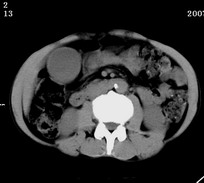

以下是引用zjzjr在2007-9-15 22:24:00的发言:[br]胰头钩突略饱满,肝内外胆管略扩张,胆囊积水.建议增强扫描.

以下是引用代课学生在2007-9-16 10:20:00的发言:[br]胆总管中段以上胆管均示扩张,考虑胆总管下段/胰头部病变,建议增强或micp检查。